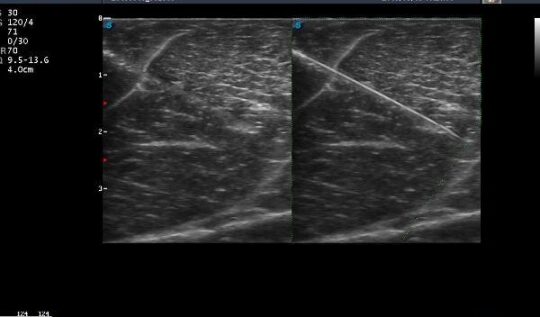

Imaging interventistico: le nuove frontiere Nel panorama dell’ecografia interventistica, uno dei temi più discussi negli ultimi anni è la visibilità dell’ago durante procedure come biopsie, drenaggi e infiltrazioni. A novembre 2025 è stato pubblicato uno studio che segna un passo avanti significativo in questo settore: “Real-time 3D Ultrasonic Needle Tracking with a Photoacoustic Beacon”, un progetto di ricerca che ha…